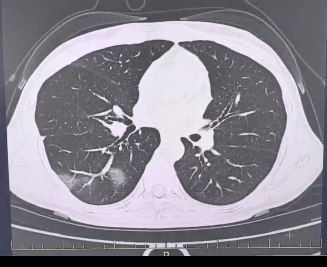

在门诊“硬抗”了3天后,程女士在工作会议中不住地咳嗽,严重的呼吸困难更让她无法集中精力工作。一测体温,39.7℃!同事们见状,将她再次送到市三医院呼吸内科。接诊的呼吸内科主任冷报浪主任医师了解到她口服速福达抗流感病毒后,仍反复发热,并咳出黄色浓痰后,立即安排了相关检查。结果情况反而进一步加重:好几叶肺都出现了“白肺”现象,指间血氧饱和度只有88%,血心肌酶谱、肌钙蛋白的指标、肝功能的指标也出现了明显的异常。流感(重型)!程女士立即被安排住院治疗。医院呼吸科团队迅速制定了一套个性化的诊疗方案,在悉心救治下,7天后,程女士顺利康复出院。

肺炎 图片来源于稿源单位

所以,肺炎也是流感最常见的并发症之一,可引发包括原发流感病毒性肺炎、继发细菌性肺炎、细菌和病毒混合感染性肺炎,会有高热、咳嗽、咳痰、呼吸困难等症状,严重时可出现呼吸衰竭。